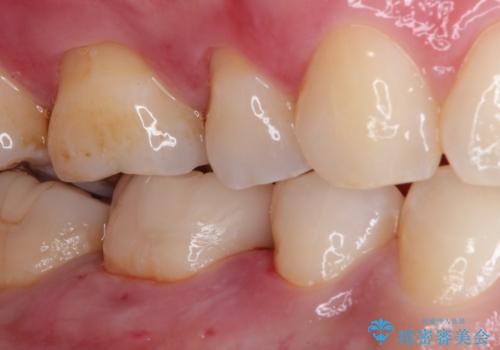

審美性の高いセラミックインレー

- メタルインレーによる審美障害を主訴に来院されました。

セラミックインレーに治療を行っております。

e-max プレスインレーにて修復治療を行っているため適合性及び審美性の高い治療を行うことができます。